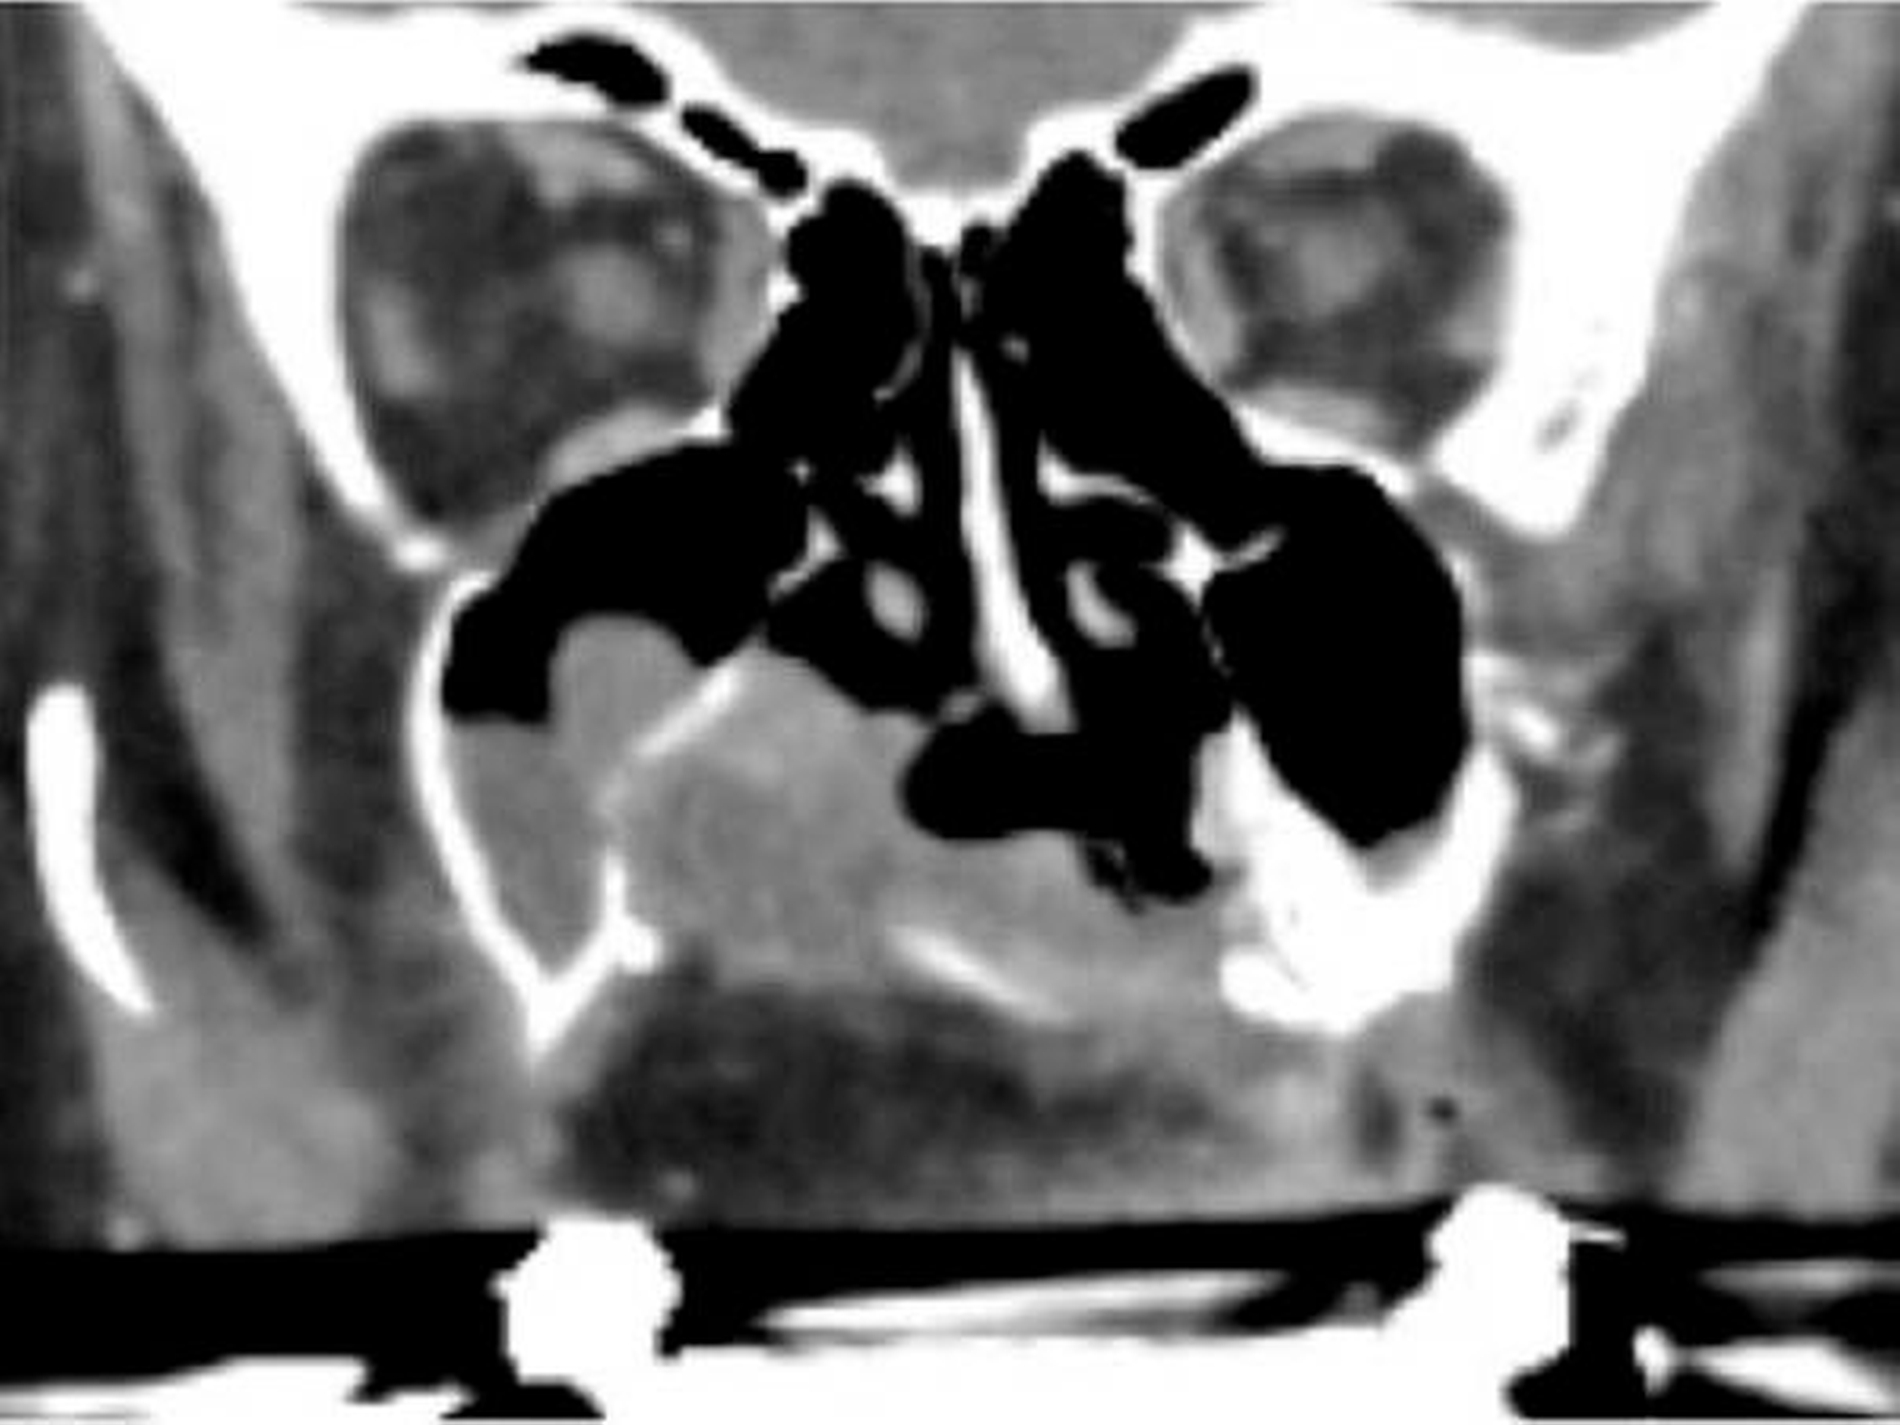

Die computertomografische Bildgebung zeigte eine inhomogene, kontrastmittelanreichernde und mittellinienüberschreitende Raumforderung im Bereich des Gaumens, die kaudal in die Mundhöhle und kranial in das Cavum nasi reichte. Die Größenausdehnung betrug circa axial 67 x 56 x kraniokaudal 52 mm.

Der Tumor wies multiple hypodense Anteile und einzelne Kalzifikationen auf. Die rechte Maxilla war distal der Regio 24 destruiert. Auch das Palatum durum et molle zeigten beidseits (rechtsbetont) Osteolysen bei primär verdrängendem Charakter auf. Der Nasopharynx war subtotal verlegt, die Uvula, der rechte M. constrictor pharyngis superior und beide Choanen nicht mehr abgrenzbar.

Der Tumor ragte durch die mediale Begrenzung des rechten Sinus maxillaris in die Nasenhaupthöhle mit einer hauchdünnen knöchernen Begrenzung. Rechts reichte die Raumforderung bis in die Fossa pterygoidea. Die Processus pterygoidei waren zentral aufgelöst. Rechtsseitig war die Anzahl der Lymphknoten in Level Ib und IIa/b vermehrt und moderat vergrößert, aber ohne klare Malignitätskriterien.